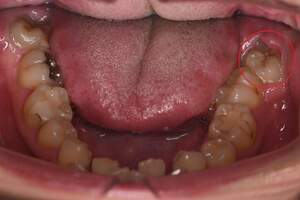

左下の歯茎が腫れている親知らずの症例

左下の親知らず周囲歯肉が腫れていました。

また、手前の歯との間で虫歯もできていました。

口腔内

半埋伏の親知らずでした。3糸縫合しました。